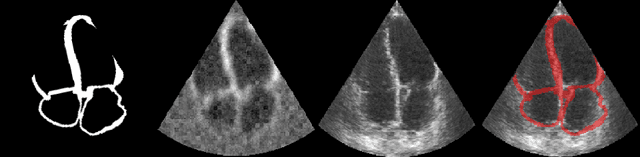

Abstract:Echocardiography plays a fundamental role in the extraction of important clinical parameters (e.g. left ventricular volume and ejection fraction) required to determine the presence and severity of heart-related conditions. When deploying automated techniques for computing these parameters, uncertainty estimation is crucial for assessing their utility. Since clinical parameters are usually derived from segmentation maps, there is no clear path for converting pixel-wise uncertainty values into uncertainty estimates in the downstream clinical metric calculation. In this work, we propose a novel uncertainty estimation method based on contouring rather than segmentation. Our method explicitly predicts contour location uncertainty from which contour samples can be drawn. Finally, the sampled contours can be used to propagate uncertainty to clinical metrics. Our proposed method not only provides accurate uncertainty estimations for the task of contouring but also for the downstream clinical metrics on two cardiac ultrasound datasets. Code is available at: https://github.com/ThierryJudge/contouring-uncertainty.

Abstract:We propose a novel pipeline for the generation of synthetic images via Denoising Diffusion Probabilistic Models (DDPMs) guided by cardiac ultrasound semantic label maps. We show that these synthetic images can serve as a viable substitute for real data in the training of deep-learning models for medical image analysis tasks such as image segmentation. To demonstrate the effectiveness of this approach, we generated synthetic 2D echocardiography images and trained a neural network for segmentation of the left ventricle and left atrium. The performance of the network trained on exclusively synthetic images was evaluated on an unseen dataset of real images and yielded mean Dice scores of 88.5 $\pm 6.0$ , 92.3 $\pm 3.9$, 86.3 $\pm 10.7$ \% for left ventricular endocardial, epicardial and left atrial segmentation respectively. This represents an increase of $9.09$, $3.7$ and $15.0$ \% in Dice scores compared to the previous state-of-the-art. The proposed pipeline has the potential for application to a wide range of other tasks across various medical imaging modalities.

Abstract:Accurate uncertainty estimation is a critical need for the medical imaging community. A variety of methods have been proposed, all direct extensions of classification uncertainty estimations techniques. The independent pixel-wise uncertainty estimates, often based on the probabilistic interpretation of neural networks, do not take into account anatomical prior knowledge and consequently provide sub-optimal results to many segmentation tasks. For this reason, we propose CRISP a ContRastive Image Segmentation for uncertainty Prediction method. At its core, CRISP implements a contrastive method to learn a joint latent space which encodes a distribution of valid segmentations and their corresponding images. We use this joint latent space to compare predictions to thousands of latent vectors and provide anatomically consistent uncertainty maps. Comprehensive studies performed on four medical image databases involving different modalities and organs underlines the superiority of our method compared to state-of-the-art approaches.